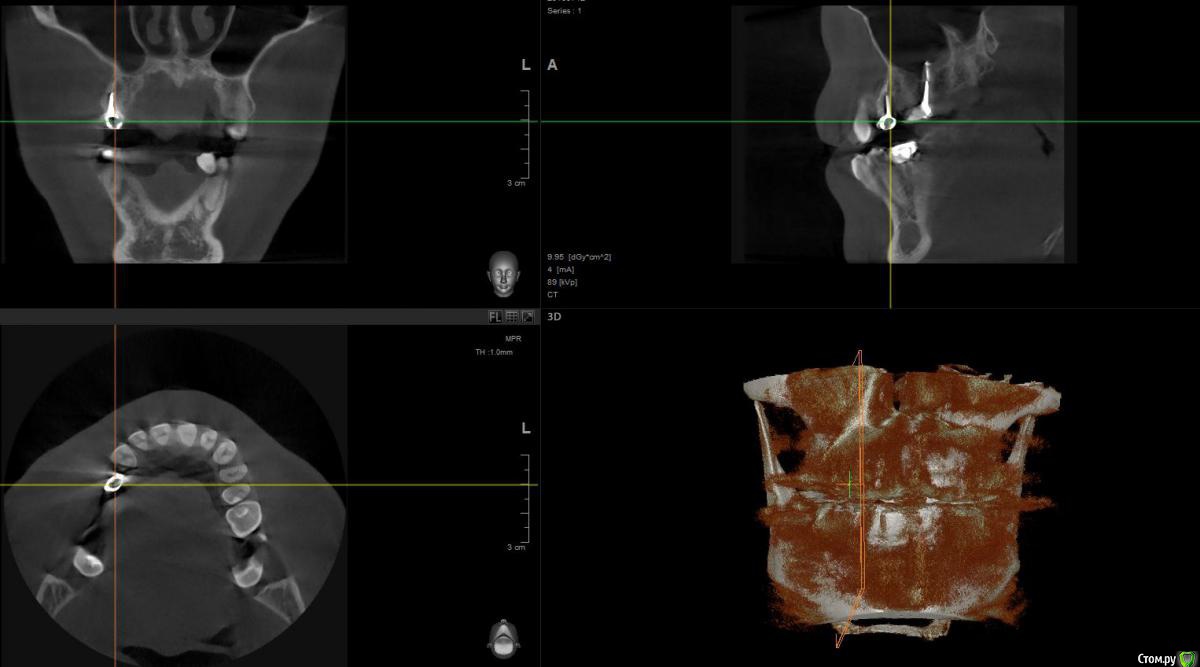

1 год назад были установлены 3 коронки. см Фото. После появления свища над верхней коронкой обратился к стоматологам.На фото 2 верхние коронки уже спилены и начато повторно лечение одного зуба,за мой счет конечно.

По результатам снимков след.вывод. Две верхние коронки снимать и лечить каналы , так там воспаление. Под нижней коронкой небольшое воспаление,но сказали пока его не трогать ,но взять под наблюдение.

post-48565-0-70633900-1469537783_thumb.jpg